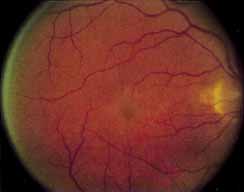

During the early stage of the dystrophy, when patients demonstrate a slight-to-moderate decrease in visual acuity and minimal color defects, there are minor or no visible fundus abnormalities. At most, the foveal reflex may be absent and there may be some increased granularity of the retinal pigment epithelium in the macula. Later, there is a decrease of visual acuity to the 20/400 range, oval atrophy of the macular retinal pigment epithelium (“beaten bronze” atrophy), and associated choroidal atrophy (Fig. 3). A characteristic bull's-eye maculopathy, similar to that seen in patients with chloroquine retinopathy, may also be seen.90 Photophobia, occasional nyctalopia, incomplete-to-complete color defects, and a central scotoma are often present. The symmetry of the process in both eyes is remarkable.

Fluorescein angiography demonstrates increased transmission of choroidal fluorescence in the macula during early phases of the study, without late leakage of dye or fluorescein staining. In addition, an annular pattern of hyperfluorescence is often seen in the macula, highlighting the bull's-eye pattern seen on fundus examination (Fig. 4). Visual field defects include central scotoma, peripheral field loss, and ring scotoma.